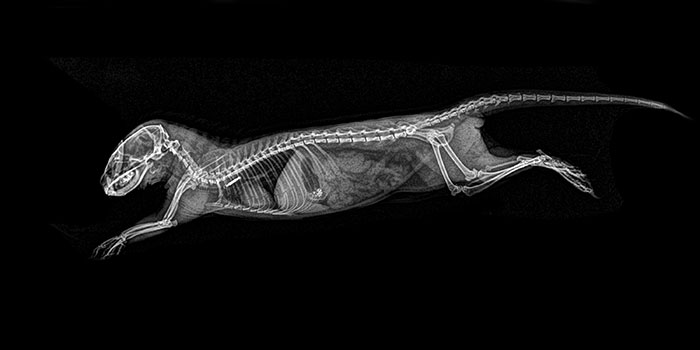

Dwarf Mongoose